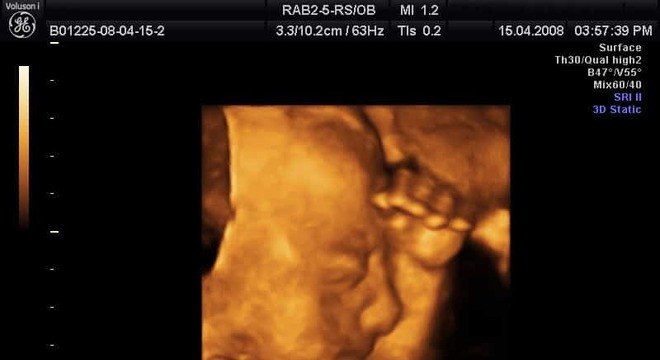

O ultrassom 3D é o nome mais curtinho do exame chamado de ultrassonografia tridimensional. Esse procedimento é simples, indolor e não invasivo, mas que ajuda a converter as ondas de som emitidas pelo corpo do bebê em imagem. Por isso, é possível ver todos os movimentos e cada pedacinho do novo integrante da família!

O funcionamento do ultrassom 3D é como uma máquina fotográfica superpotente, que tira milhares de fotos do bebê e as transforma em imagens tridimensionais. Por isso você consegue ver o rostinho com mais clareza. Além disso, o ultrassom 3D pode ser uma ferramenta poderosa na hora de avaliar quaisquer complicações na gravidez.

A indicação para quem quiser fazer o ultrassom 3D é entre a 26ª e 30ª semana de gestação (2º trimestre), exceto em caso de recomendação médica diferente. Isso porque, nesse período, é possível ver com mais detalhes o bebê, não só a estrutura óssea. Depois da 30ª semana, o espaço dentro do útero se torna menor e, com isso, diminuem as chances de vislumbrar o rostinho.

Dependendo da posição do bebê, da coloração, estrutura e volume do líquido amniótico, a visibilidade pode ser maior ou pior. É difícil conseguir prever antes do exame, mas conversar com ele pode ser uma forma de fazê-lo mexer e mostrar o rostinho.